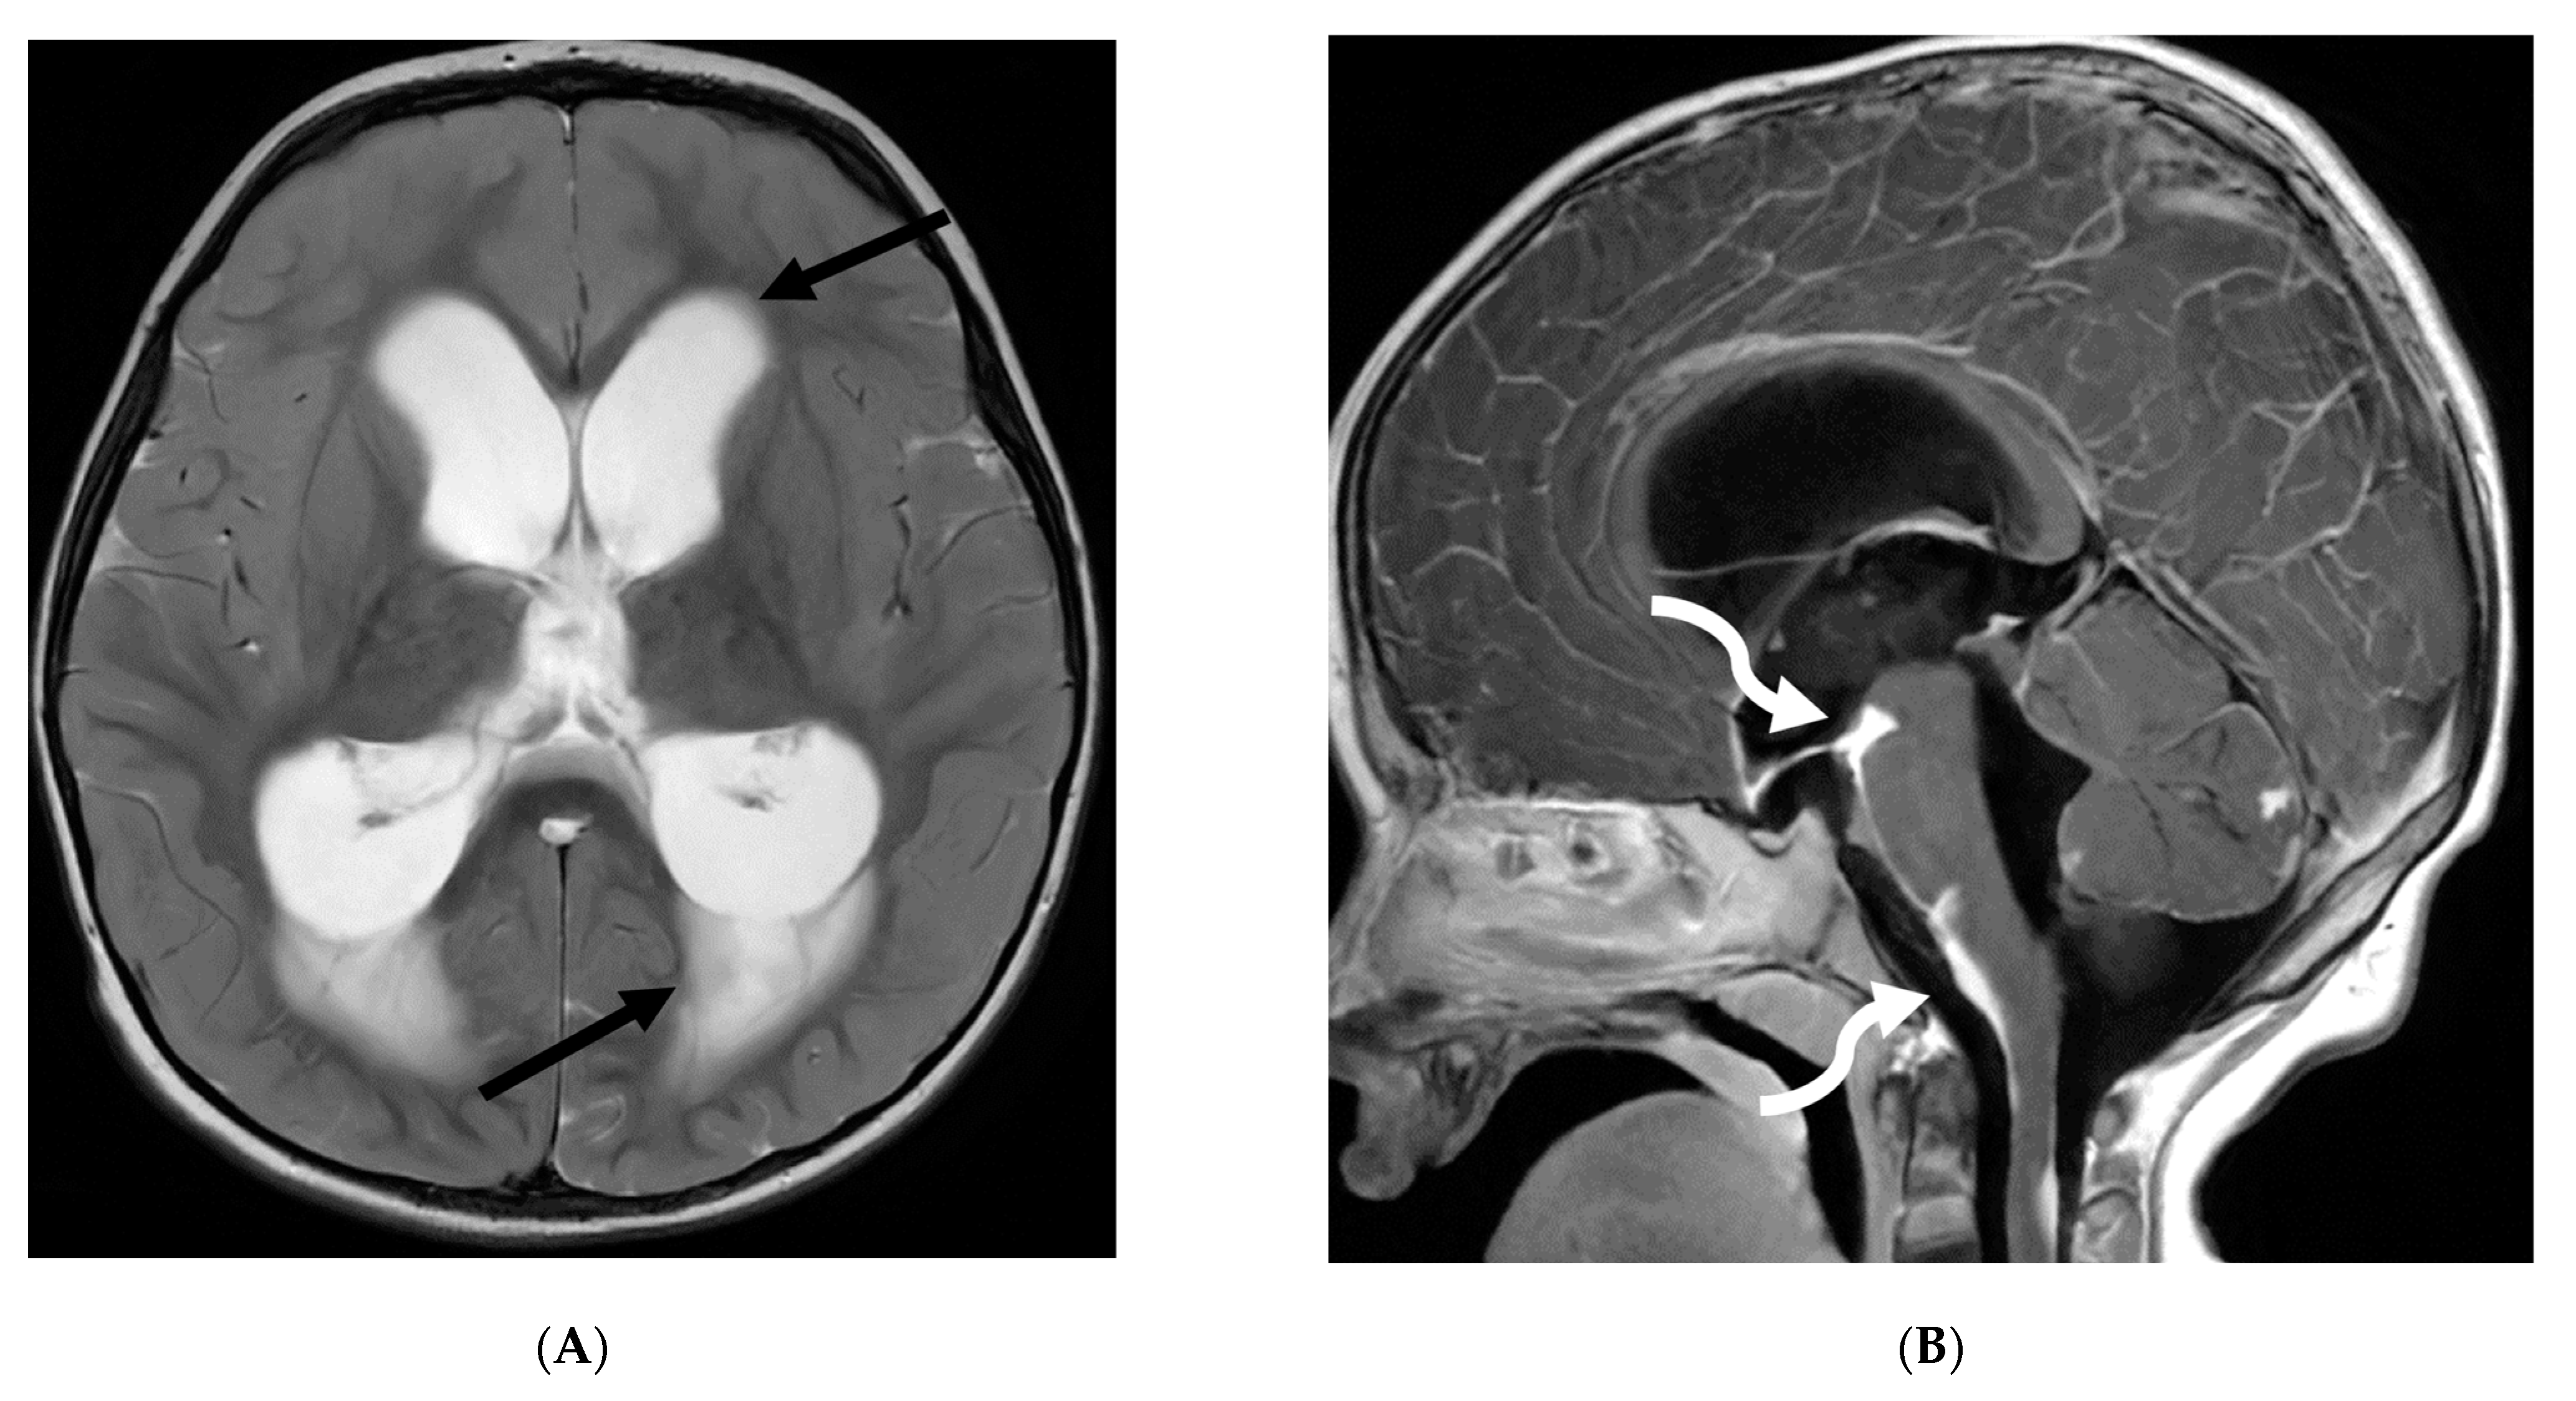

Prototheca species are unicellular algae that are typically known to involve the cutaneous and subcutaneous tissues in humans [6]. Systemic involvement, although rare, can cause meningitis, peritonitis, endocarditis, etc. and is commonly seen in immunodeficient individuals [7]. Prototheca spp. infections are usually exogenous and associated with traumatic inoculation from contaminated soil or water. They can also occur from surgery or catheterization, and even insect bites [8]. Exposure leads to chronic granulomatous inflammation with necrosis [6]. Notably, diagnosis of protothecosis may be challenging as it is not easily identified on Hematoxylin and eosin (H&E) or routine fungal stains, and mimics many fungal infections such as Coccidiodes, Blastomyces. Imaging findings include diffuse LME along the cortical sulci and spinal cord, with multiple loculations given the chronic inflammatory response. These loculations characteristically cause mass effect leading to a flattened and deformed spinal cord (Figure 2) [9].

Figure 2.

Post contrast sagittal T1 brain (A), T1 spine (B), axial T1 brain (C) and spine (D): 17-year-old girl with couple of years of fatigue, shuffling gait, back/lower extremity pain. There is moderate ventriculomegaly (white star). Meningeal enhancement is present around the cervical cord (white arrow). Flattened and deformed brainstem & spinal cord diffusely (curved arrows) and enhancing septae (dashed arrows) within the thecal sac are noted likely from chronic meningitis. Basal cistern enhancement (open arrow) and septae (arrow head) in the lateral ventricles likely reflects sequela of chronic inflammation/infection. Pathology: Prototheca Zopfil.